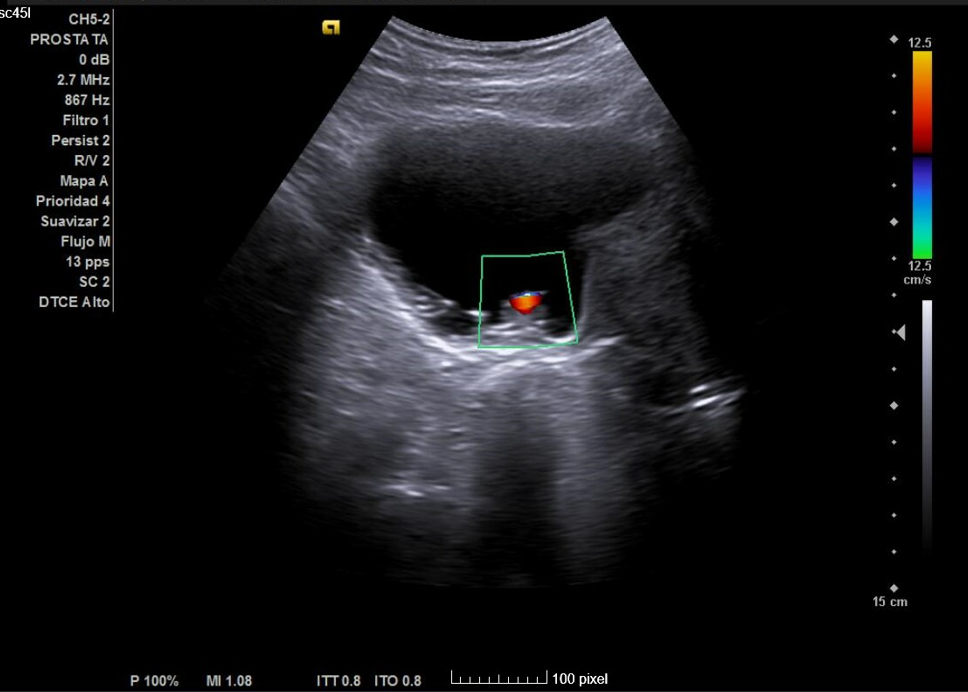

Primera ecografía: Riñón derecho de 9,6 cm, izquierdo de 9,5 cm, escoestructura y morfología normales. Vejiga con aumento de grosor de pared, residuo premiccional y posmiccional similares en torno a 350 cc (probable vejiga de lucha). Pólipo vesical a expensas de pared inferior izquierda de 18,5 x 8,7 mm. Jet ureteral bilateral conservado. Próstata de 110 cc. Se repite ecografía al mes: Pólipo vesical de 14 x 9,7 mm, próstata de 119 cc, vejiga con volumen premiccional 469 ml y posmiccional 400 ml.